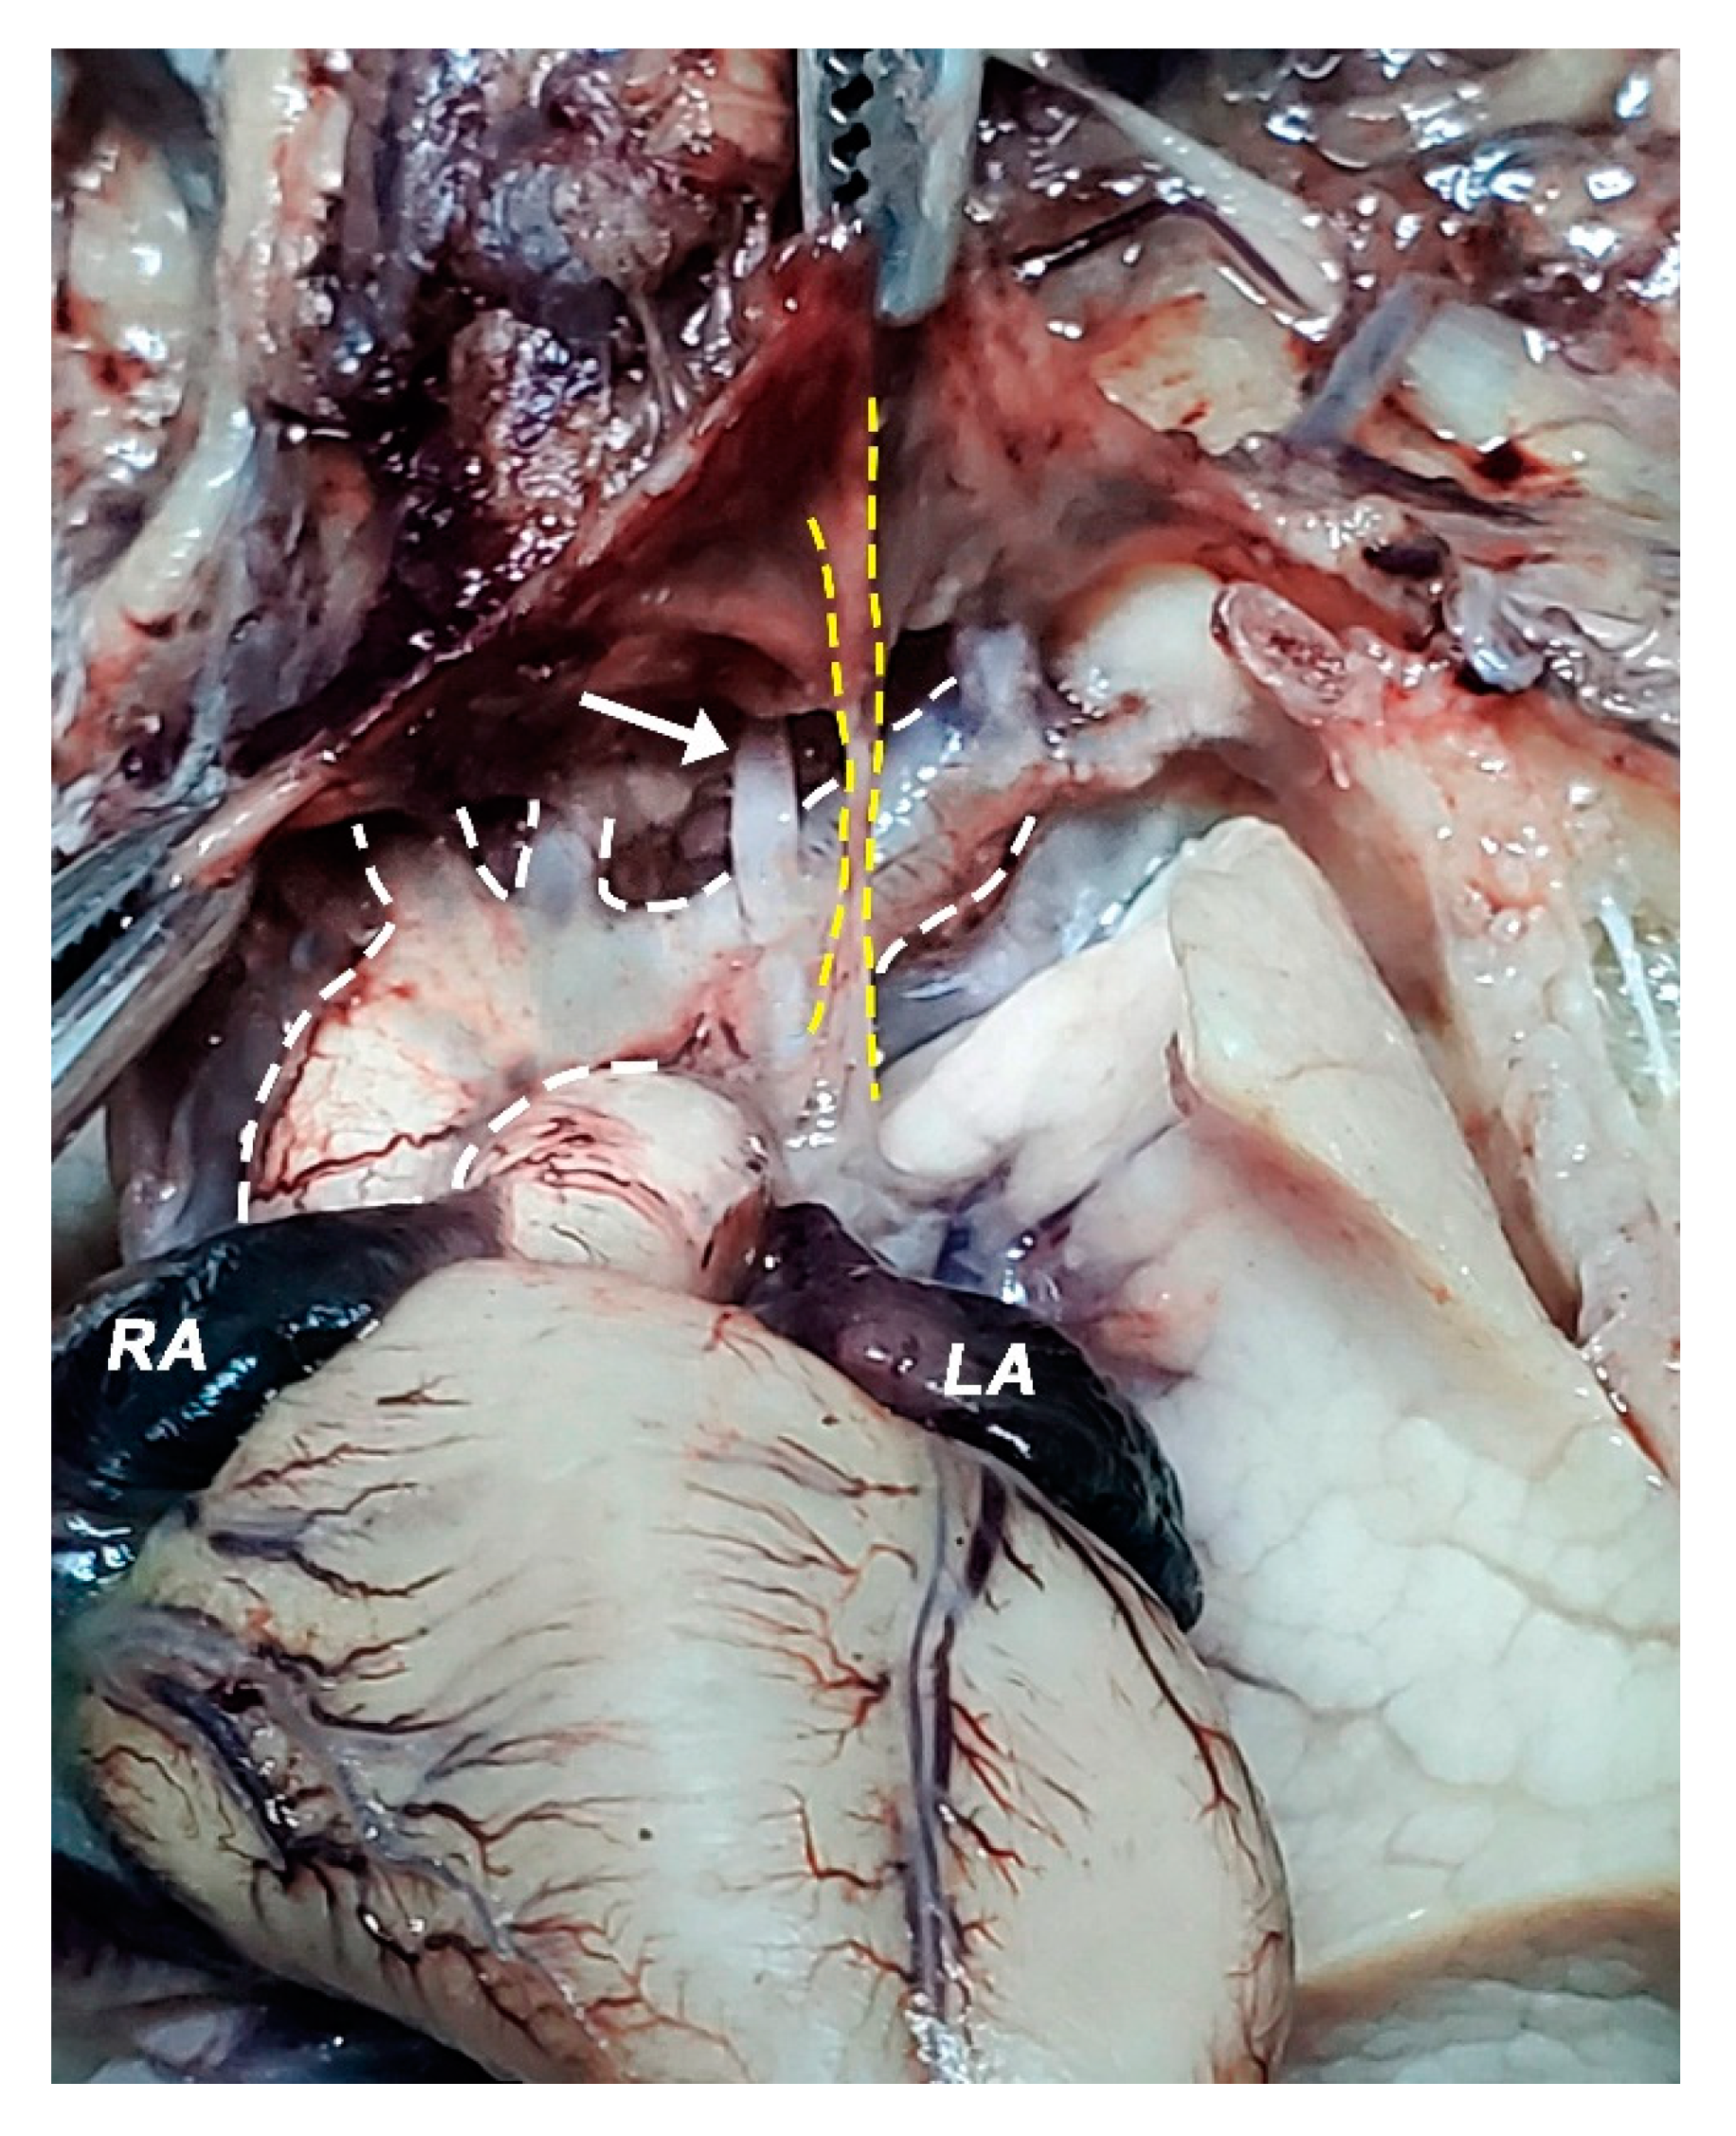

2.2. Dissection